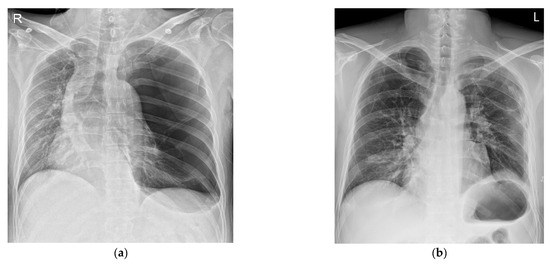

Other diseases and surgical history were denied. His vital signs in the emergency room were stable with a blood pressure (BP) of 145/90 mmHg, a heart rate (HR) of 89 bpm, a respiratory rate of 20 per minute, a SpO2 level of 97%, and a body temperature of 36 °C. An abdominal CT scan showed active bleeding in the right rectus sheath muscle and hemoperitoneum. Thus, emergency surgery was decided upon. There were no abnormal preoperative laboratory findings or electrocardiographic findings. A chest X-ray showed a large radiolucent area of the left lung with contralateral mediastinal deviation, so the emergency medicine physician suspected a pneumothorax. The pneumothorax seen on the X-ray was large, but the patient had no pneumothorax symptoms, such as dyspnea or chest pain. Therefore, a chest CT was performed. However, the CT showed a GEB in the left lung and bullous emphysema in the right lung with displacement of the mediastinal structures (Figure 1a and Figure 2a). In cases with GEBs, unlike with a pneumothorax, chest tube drainage (CTD) is not placed because the bullae could be damaged and tension pneumothorax could occur. Although the patient had no symptoms of dyspnea, it was decided to remove the GEB first and then perform abdominal surgery in consultation with a thoracic surgeon, since the GEB could affect the patient’s vital signs during positive pressure ventilation.

After the bullectomy, the supine position was changed, and surgery was performed for the abdominal wound area. For the surgical operation, laparotomy was performed. His vital signs were stable during the abdominal surgery. The patient recovered from anesthesia with stable vital signs. The total time under anesthesia was 245 min, and the operation’s time was 215 min. The patient was transferred to the intensive care unit, where his vital signs remained stable. The patient was transferred from the intensive care unit to the general ward after 16 h. A chest X-ray taken on the second day after the surgery showed no special findings (Figure 1b). The chest tube drainage was removed on the 8th day after the operation. The patient was discharged without complications on the 12th day after the operation.

For the diagnosis of a GEB, a chest X-ray is primarily performed. X-ray findings have shown large bullae that account for one-third of the hemithorax, lung parenchyma atelectasis, inverted ipsilateral diaphragm, and contralateral displacement of the mediastinum [8]. GEBs and pneumothorax are different in chest X-rays. In the chest CT scan, there was no pneumothorax, but giant bullae were shown over the entire lung. In the case of a GEB, the entire parenchyma is compressed downward in the direction of the costal angle, while a pneumothorax appears as a lung parenchyma that collapses into a clump toward the hilum [9]. However, plain chest X-rays and physical examinations cannot provide accurate anatomical information on the findings. In addition, if a CTD is mistakenly inserted for a pneumothorax, the GEB, which has a very thin wall compared to the normal lung parenchyma, is easily damaged and can lead to a dangerous situation, such as tension pneumothorax. Therefore, chest CT is more appropriate as a test for differentiating GEBs [10]. CT can also be a good test, as it can diagnose other coexisting diseases. In the present case, the left lung was radiolucent on chest PA, and the mediastinum was deviated to the right, suggesting tension pneumothorax (Figure 1a). In the chest CT scans, it was revealed that it was not a pneumothorax, as giant bullae were shown over the entire lung. These giant bullae caused a mass effect that deviated the mediastinum (Figure 2a). In addition, it could be seen that the inferior vena cava (IVC) was bent due to the mediastinal shift in the coronal plane of the chest CT (Figure 2b). This can lead to cardiovascular collapse due to the mass effect of the GEB itself, as well as tension pneumothorax due to the rupturing of the GEB. We speculate that this mass effect might have been exaggerated by muscle relaxation after succinylcholine use. Superior vena cava syndrome caused by a GEB pressing the superior vena cava has been reported [11]. However, cases showing IVC-syndrome-like symptoms by pressing the IVC have not yet been reported.

Figure 1. Chest X-ray at the time of admission (a) and on the first day after the operation (b). It can be seen that the left lung collapsed, and the mediastinum shifted to the right (a).